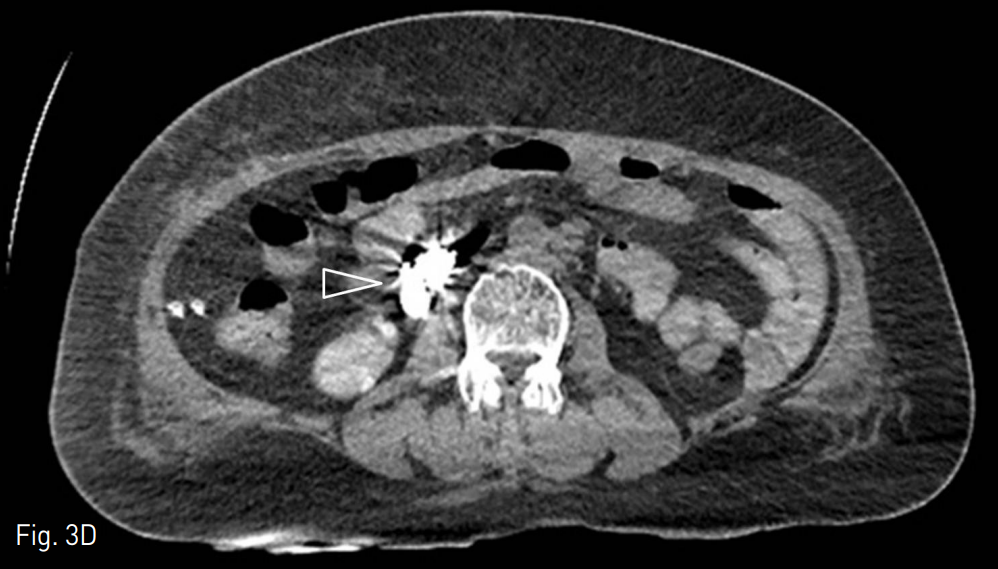

마지막 내시경적 치료 이후에 검사한 전산화 단층촬영 (CT, Computed Tomography)에서 십이지장 제3부와 제4부에 걸쳐 hemoclipping된 십이지장 정맥류가 있음 (Fig. 2A-C). 십이지장 정맥류는 상장간막정맥에서 기시하여 좌측 부신장정맥으로 연결되는 장간막신장정맥단락(mesenterorenal shunt)에 위치했음.

A. Varix with hemoclipping (arrow) is seen at the 3rd/4th portion of duodenum.